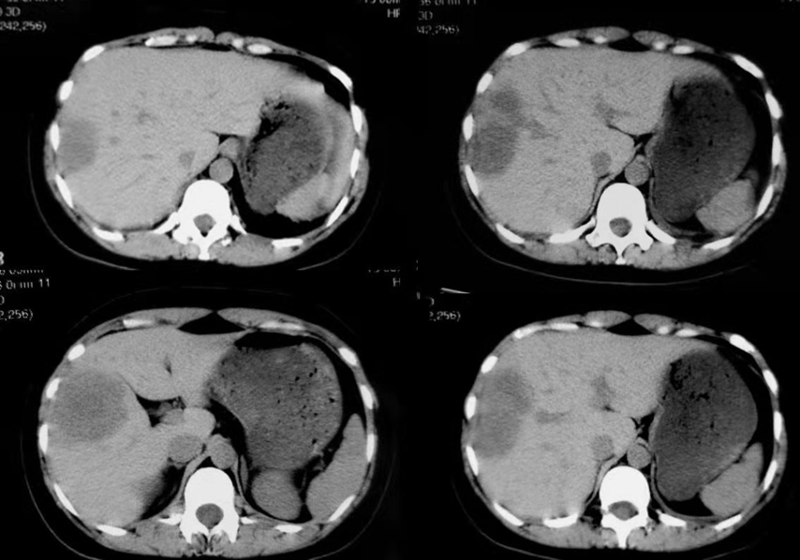

1、影像学检查:如X线胃肠道钡餐造影、CT检查、MRI检查、经直肠超声检查。腹部X线检查适用于伴发急性肠梗阻病人,可见梗阻部位上方的结肠有充气胀大现象。直肠癌术前行直肠MRI为常规检查项目,是术前分期的重要依据。

肠癌肝转移CT